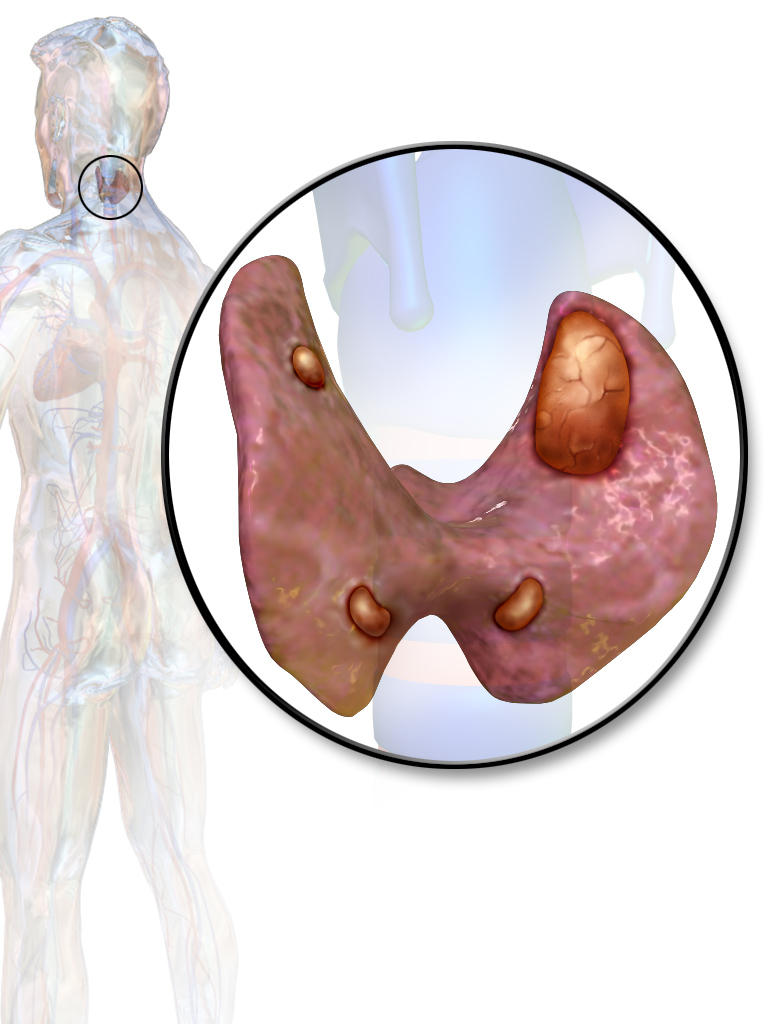

부갑상선 기능 항진증은 부갑상선 호르몬(PTH)의 과다 분비로 인해 혈중 칼슘 농도가 높아지는 질환이다. 원발성, 속발성, 삼차성으로 분류되며, 원발성은 부갑상선 자체의 문제로, 속발성은 저칼슘혈증에 대한 반응으로, 삼차성은 장기간의 속발성 부갑상선 기능 항진증으로 인해 발생한다. 방사선 노출, 유전적 요인, 리튬 및 티아지드 이뇨제 사용 등이 위험 요인으로 작용하며, 증상으로는 변비, 구토, 피로, 신결석 등이 나타날 수 있다. 진단은 혈액 검사를 통해 이루어지며, 치료는 부갑상선 절제술, 비타민 D 보충, 인 섭취 제한 등 발생 유형에 따라 다르다.

부갑상선 기능 항진증은 부갑상선 호르몬(PTH)이 과도하게 분비되어 발생하는 질환으로, 그 원인에 따라 크게 세 가지 유형으로 분류된다.

원발성 부갑상선 기능 항진증은 부갑상선 자체의 문제로 인해 부갑상선 호르몬(PTH)이 과도하게 분비되는 질환이다.[40][41] 주요 원인으로는 부갑상선 선종(환자의 80%), 부갑상선 과형성(환자의 15~20%), 드물게 부갑상선암(환자의 1% 미만)이 있다.[14] 대부분의 경우 특별한 가족력 없이 산발적으로 발생한다.[14]